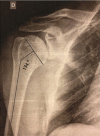

Fig. 1

Radiograph showing measurement of the cervicodiaphyseal angle of the proximal humerus, i.e. the angle between the anatomical neck and the axis of the humeral diaphysis.